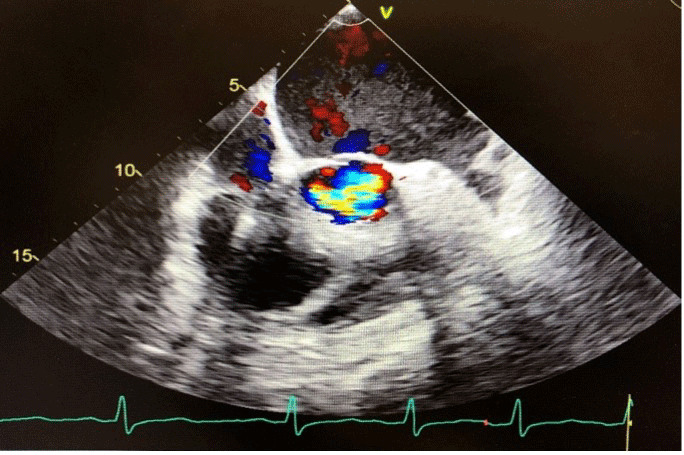

约25%被诊断患有冠状病毒病19 (COVID-19)的患者出现心血管并发症,导致40%的相关死亡。在此,我们讨论一位69岁男性,有充血性心力衰竭病史,并在纽约心脏协会(NYHA) II级保留射血分数,表现为新的呼吸困难,咳嗽和阵发性夜间呼吸困难。他随后被诊断为COVID-19肺炎,虽然他最初康复,但后来症状恶化,进展为NYHA IV级。随访超声心动图显示射血分数下降至40%,主动脉严重不全。他接受了主动脉瓣置换术,缓解了症状。该病例突出了COVID-19导致瓣膜疾病快速进展的可能性。

About 25% of patients diagnosed with coronavirus disease 19 (COVID-19) experience cardiovascular complications, contributing to 40% of related deaths. Here we discuss a 69-year-old male with a history of congestive heart failure and preserved ejection fraction at New York Heart Association (NYHA) class II who presented with new dyspnea, cough, and paroxysmal nocturnal dyspnea. He was subsequently diagnosed with COVID-19 pneumonia, and while he initially recovered, he later showed worsening symptoms with progression to NYHA class IV. Follow-up echocardiogram revealed a decline in ejection fraction to 40% and severe aortic insufficiency. He underwent surgical aortic valve replacement, resolving his symptoms. This case highlights COVID-19's potential to cause rapid progression of valvular disease.